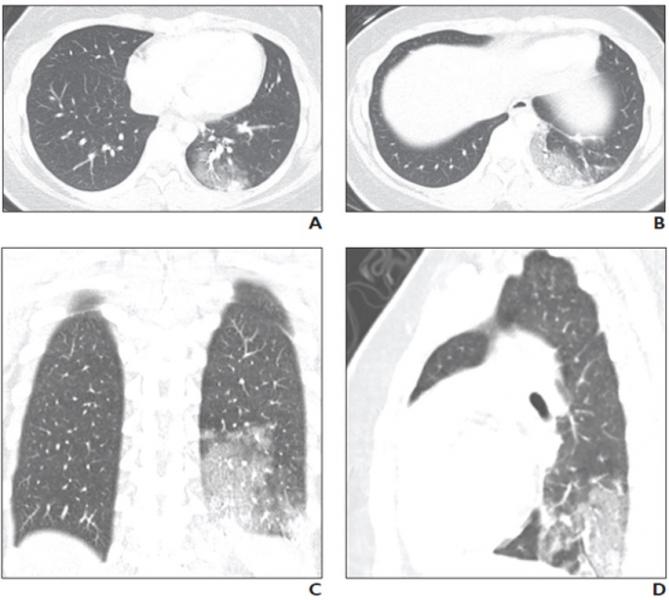

Covid 19 Pediatric Findings In New Review Of Lung Disorders Imaging Technology News

Cureus Common Ct Findings Of Novel Coronavirus Disease 2019 Covid 19 A Case Series